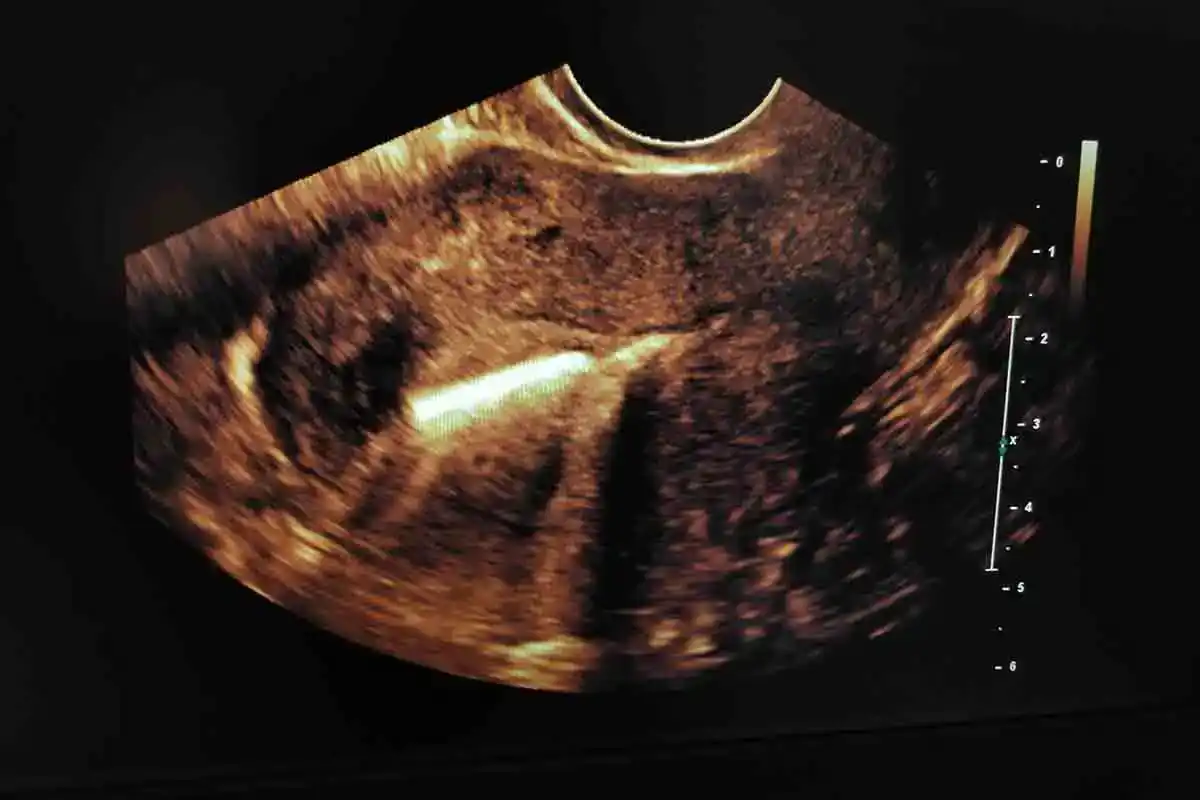

מיקום נכון של ה- IUD חשוב ליעילות ה- IUD. הרופא מחדיר מכשיר לתוך הרחם דרך צוואר הרחם.

גם כאשר רופא מיומן מחדיר התקן תוך רחמי בצורה נכונה, ההתקן עלול להיתקע בצוואר הרחם או בחלקים אחרים בגוף. זה קורה לרוב בחודשים הראשונים לאחר ההתקנה.

Votre médecin fera une échographie pour vérifier si la grossesse est viable ou extra-utérine. Une fois qu'une grossesse viable est confirmée, le DIU doit être retiré pour obtenir les résultats idéaux pour vous et votre bébé. Le fait de ne pas retirer le DIU peut augmenter le risque d’infection (avortement septique ou chorioamnionite), de fausse couche, de mortinatalité et de naissance prématurée. Cependant, si le dispositif est déplacé vers un endroit nécessitant une intervention chirurgicale susceptible de nuire au fœtus, le médecin peut décider de laisser le dispositif en place.